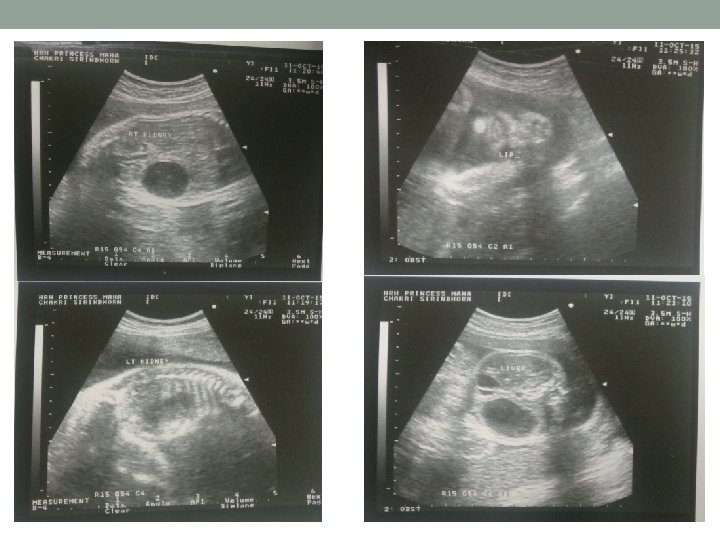

Transabdominal ultrasound(11/10/58) • Singleton fetus, intrauterine pregnancy • Cephalic presentation, EFW 1444 gm (<Percentile 5, reference จฬา ) • BPD 75. 5 mm/ 29+6 wk • HC 273 mm/ 29+4 wk • AC 251. 0 mm/ 29+2 wk • FL 55. 8 mm/ 29+3 wk • Fetal movement: positive, fetal cardiac activity: positive • AFI: 14. 2 cm

Transabdominal ultrasound(11/10/58) • Placenta: posterior middle, grade II, no placenta previa • No venticulomegaly • No cleft lips • Four cardiac chamber, not clearly seen LVOT, RVOT due to fetal position • Abdominal wall defect 2 cm, no liver protrude suspected gastroschisis • Seen both kidney, bladder